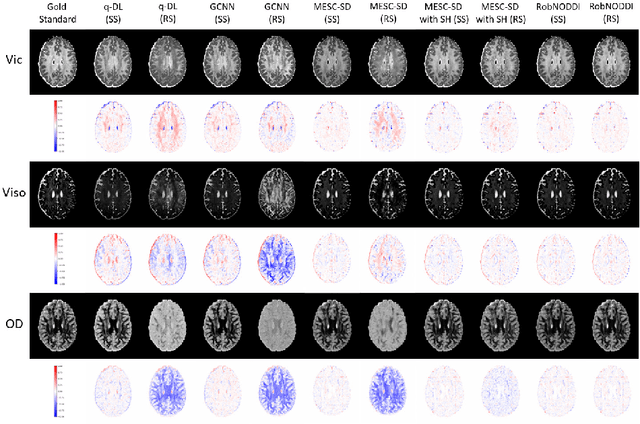

Abstract:Neurite Orientation Dispersion and Density Imaging (NODDI) is an important imaging technology used to evaluate the microstructure of brain tissue, which is of great significance for the discovery and treatment of various neurological diseases. Current deep learning-based methods perform parameter estimation through diffusion magnetic resonance imaging (dMRI) with a small number of diffusion gradients. These methods speed up parameter estimation and improve accuracy. However, the diffusion directions used by most existing deep learning models during testing needs to be strictly consistent with the diffusion directions during training. This results in poor generalization and robustness of deep learning models in dMRI parameter estimation. In this work, we verify for the first time that the parameter estimation performance of current mainstream methods will significantly decrease when the testing diffusion directions and the training diffusion directions are inconsistent. A robust NODDI parameter estimation method with adaptive sampling under continuous representation (RobNODDI) is proposed. Furthermore, long short-term memory (LSTM) units and fully connected layers are selected to learn continuous representation signals. To this end, we use a total of 100 subjects to conduct experiments based on the Human Connectome Project (HCP) dataset, of which 60 are used for training, 20 are used for validation, and 20 are used for testing. The test results indicate that RobNODDI improves the generalization performance and robustness of the deep learning model, enhancing the stability and flexibility of deep learning NODDI parameter estimatimation applications.